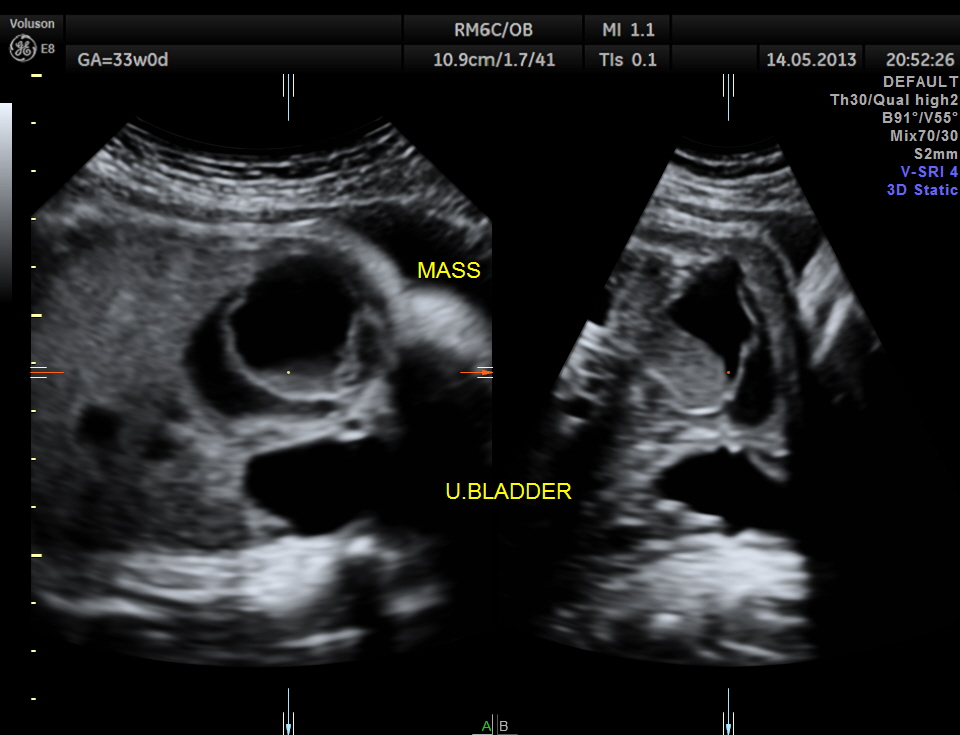

The lower abdomen showed a predominantly cystic mass with septations and internal echoes .

This was distinct from the urinary bladder and the kidneys. Both the kidneys showed mild pelviectasis.

The diagnosis offered was probable ovarian cyst with a D.D. of mesenteric cyst

I wouldn’t think it’s a dermoid without seeing any calcifications right away. I don’t see any pictures with color flow to show if there was flow with the septation or ? tissues. By any chance, did you optain any?

There was no flow picked up